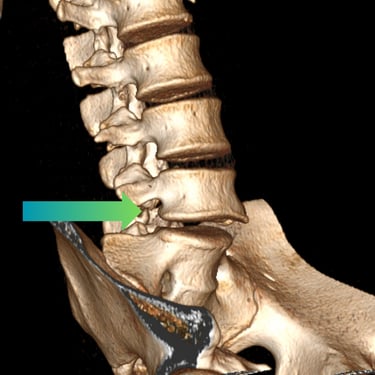

Listesis Lumbar L5–S1 por Fractura Ístmica: Estabilización con FTP y TLIF

La listesis lumbar L5–S1 por fractura ístmica se produce por un defecto en la pars interarticularis que genera inestabilidad vertebral, dolor lumbar crónico y compromiso radicular. Cuando el tratamiento conservador no es efectivo, la artrodesis lumbar con fijación transpedicular (FTP) asociada a la fusión intersomática transforaminal (TLIF) es una alternativa quirúrgica eficaz. Este procedimiento permite descomprimir las raíces nerviosas, restaurar la alineación vertebral y lograr una fijación sólida del segmento afectado. La combinación de estabilización y fusión reduce el dolor, mejora la función y favorece una recuperación segura y progresiva.